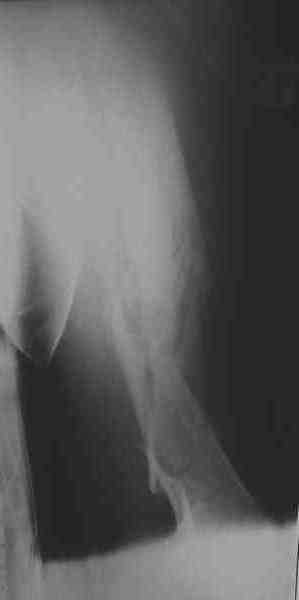

Уважаемые коллеги! Пришел на консультацию вот такой больной (первые 3-и рисунка). Травма автодорожная, апрель 2006г. Лечился консервативно, вытяжение и гипс. Через пять месяцев стал ходить. Укорочение бедра 6 см. 26 февраля 2007г. оступился, упал. Прооперирован в г.Баку - наложен стержневой аппарат. Ходит с костылями, наступая на левую ногу. Мы попросили что нибудь из ранних снимков. Принес рентгенограммы перелома (рис. 4,5). Посмотрели, наснимали сами (рис. 6-10). Похоже, что нет сращения нигде. Хотелось - бы обсудить следующие вопросы:1. дальнейшая тактика - реостеосинтез или подождать (ослабить аппарат, дать нагрузку и т.д.)?2. если реостеосинтез - то чем и как? Юрий Алексеевич Булахтин